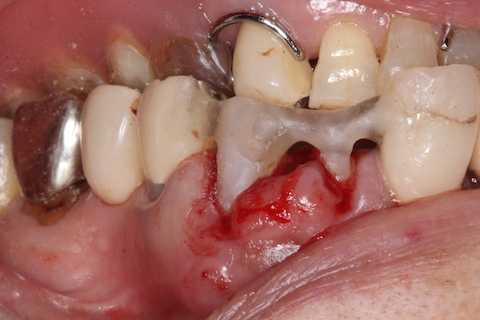

普通にズブズブと抜歯窩に再建した歯根を挿入する。

あとは接着固定しながら、歯冠を再建していく。